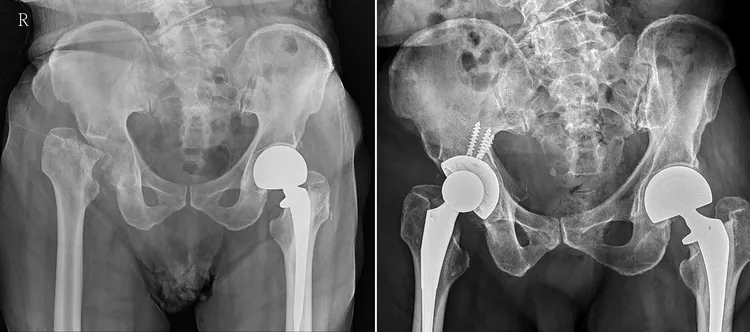

洪舜奕医师说,经骨科检查与影像学确认,发现该老翁的右脚股骨头早已断裂并陷入髋臼关节腔内,已导致双脚长短相差达4公分。认定该患者实际上一年前跌倒时就发生了股骨颈骨折,但未被正确诊断,导致长期错位与骨坏死,碎骨嵌入骨盆与髋臼关节,饱受疼痛与关节受限之苦。

患者接受进行人工全髋关节置换手术,取出关节内碎裂的骨头、沾黏的软组织,重建髋臼与股骨之间的稳定关节,并将腿长恢复至正常长度。术后患者疼痛明显改善,经术后复健,目前已能正常行走。